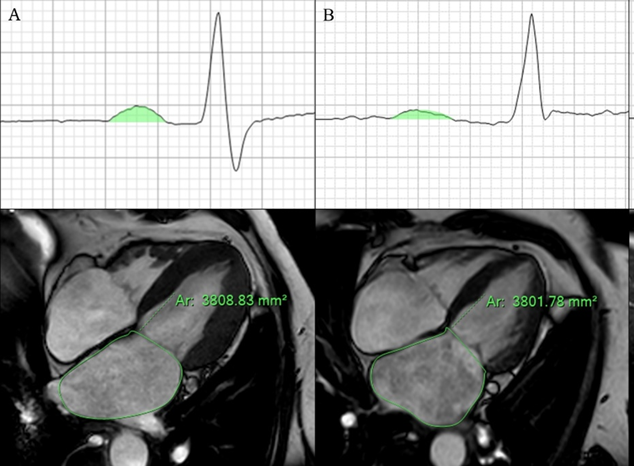

Patients undergoing first-time PVI were included in the analysis. A 12-lead electrocardiogram (ECG) in sinus rhythm was recorded prior to the procedure, and cardiac magnetic resonance imaging (CMR) (Ingenia 1.5T Philips) was performed to assess left atrial (LA) area. The PWAi was calculated by indexing the P-wave area in leads II to the LA area (PWAi = P-wave area / LA area, Figure 1). The primary outcome was AF recurrence during follow-up. Kaplan-Meier survival analysis was used to evaluate the association between PWAi and recurrence risk.

Figure 1:

P Wave Area in lead II and left atrial Area in patients (a) without and (b) with present atrial myopathy and AF recurrence